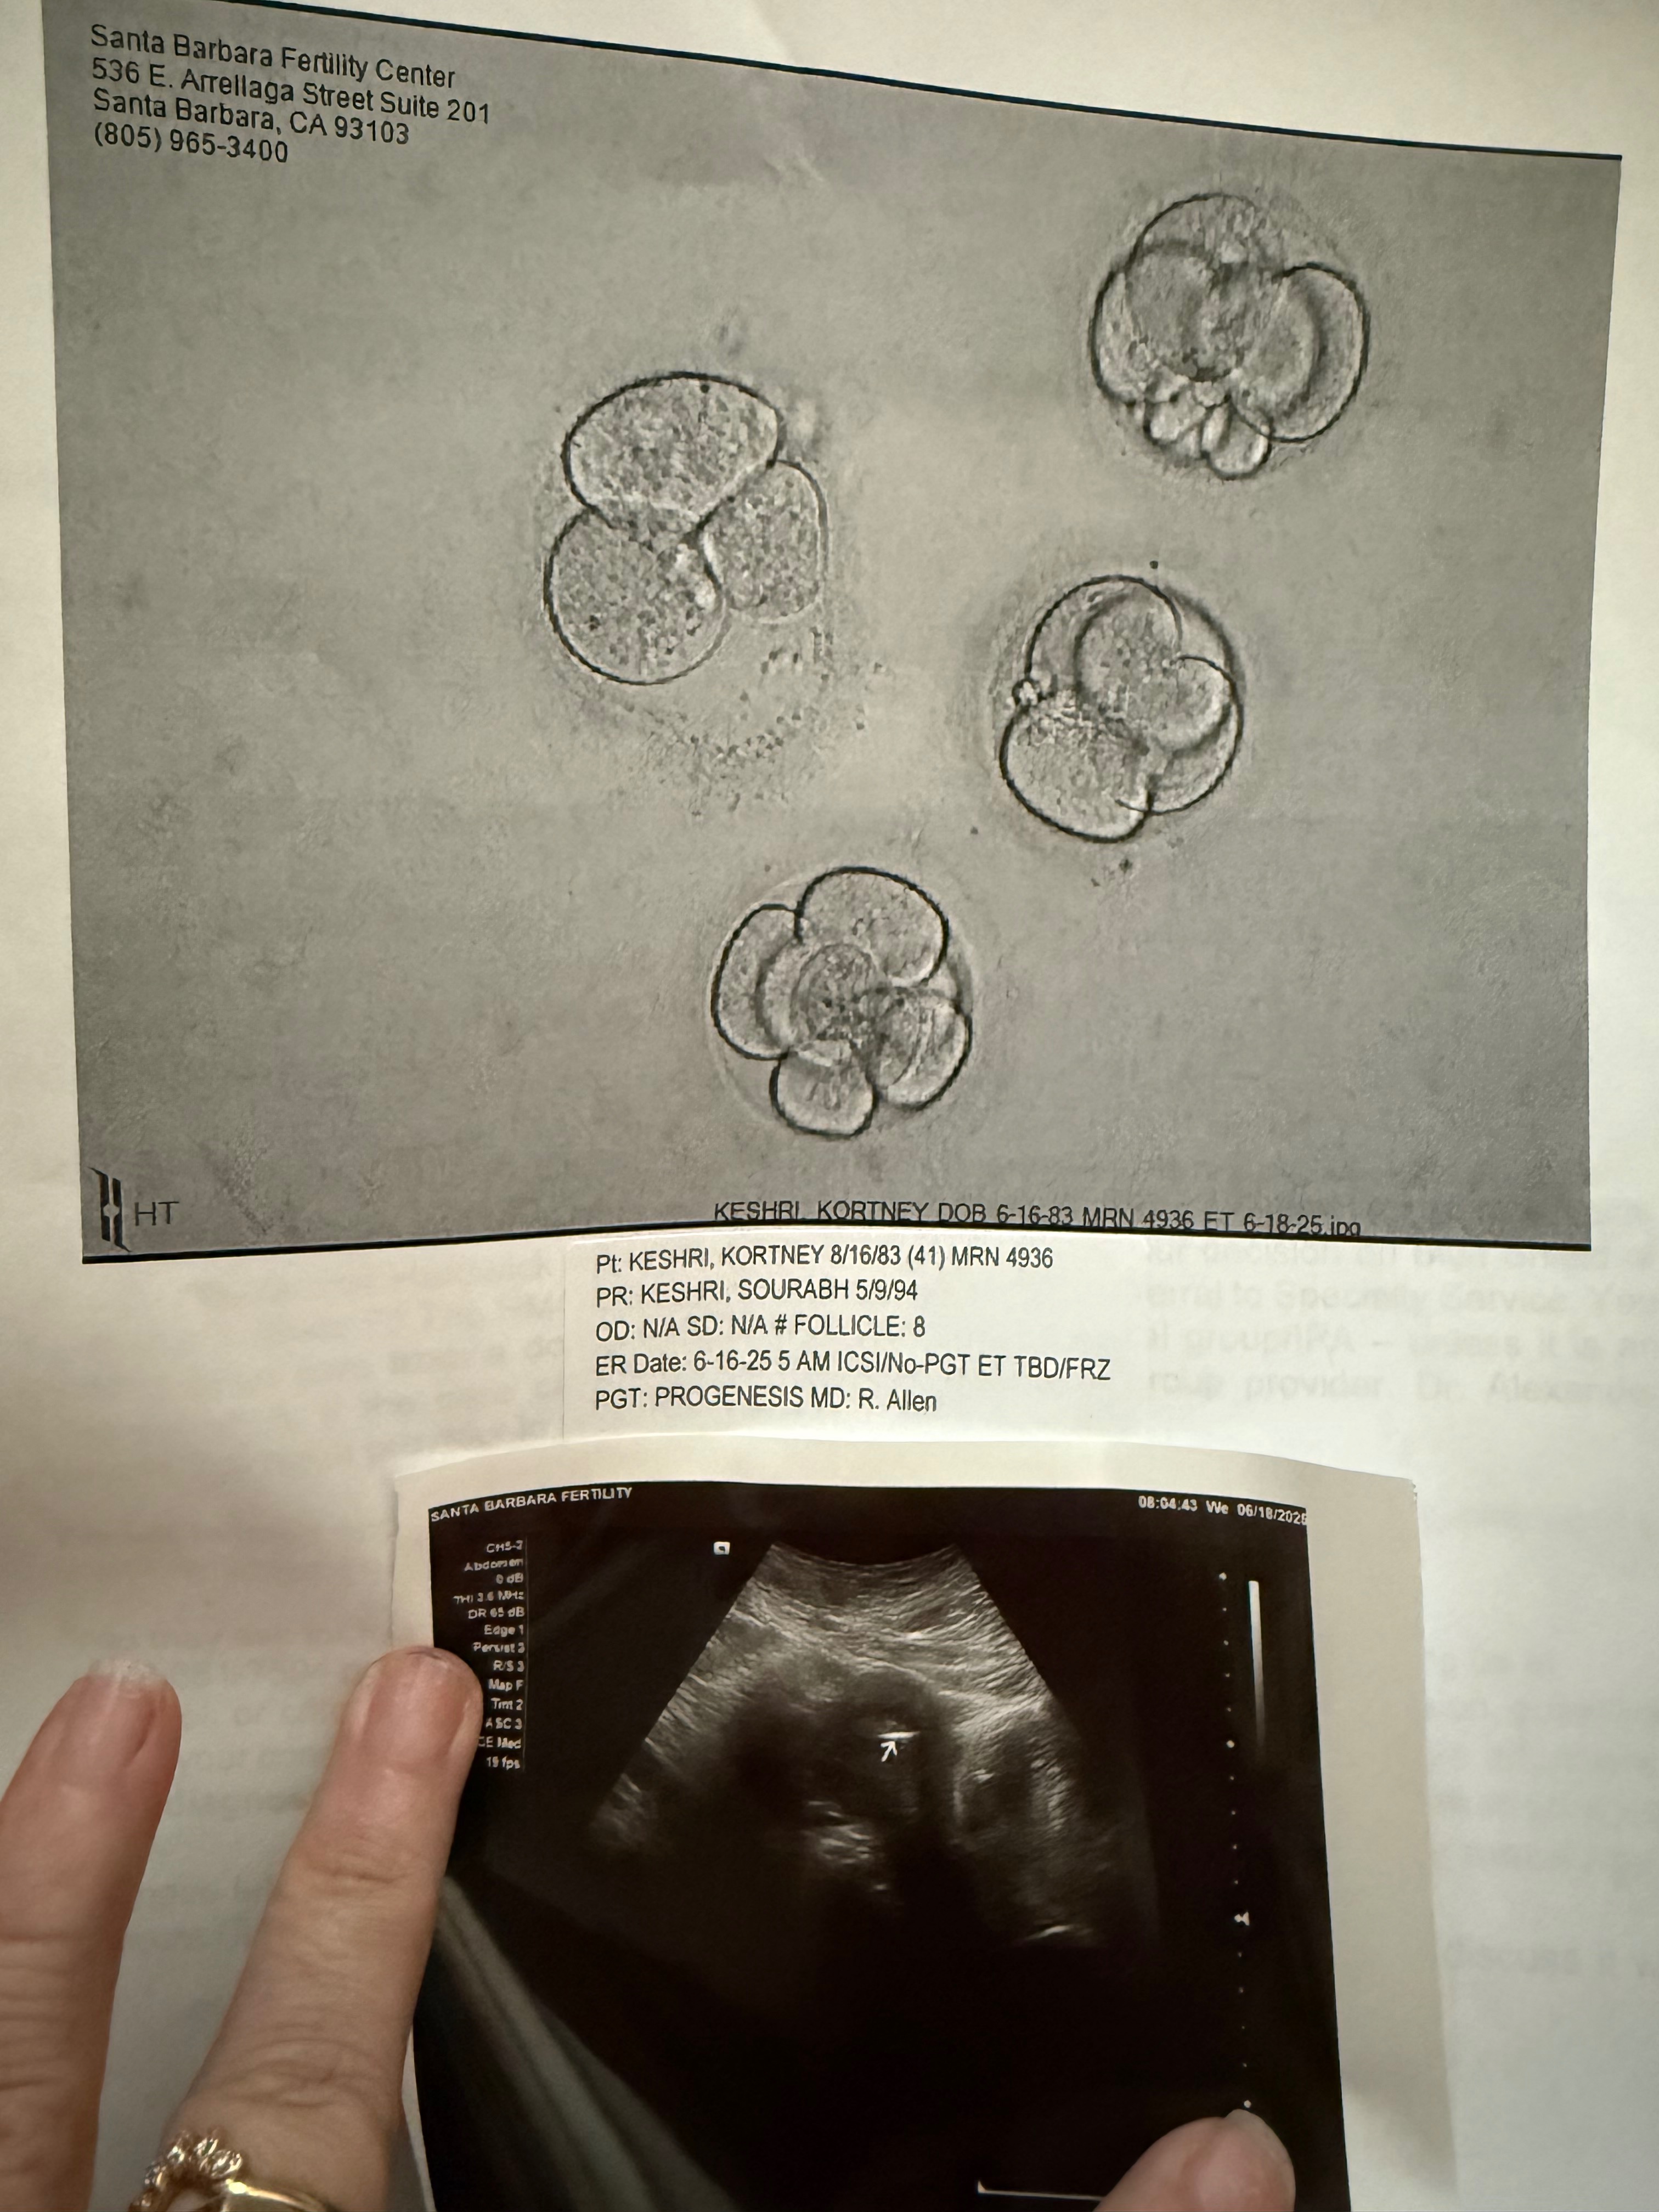

We are Sourabh & Kortney Keshri living in Santa Barbara, CA. We just finished an unsuccessful round of IVF. After 73 injections, 104 pills, 8 blood draws, and 1 dye test… our IVF journey ended in heartbreak. 7 eggs were retrieved, 5 were mature, and 4 were fertilized and transferred back into my uterus, but none stuck. We collected a lot of baby items, planned out names, and really thought our dream would happen, but it didn’t in the first round of IVF.